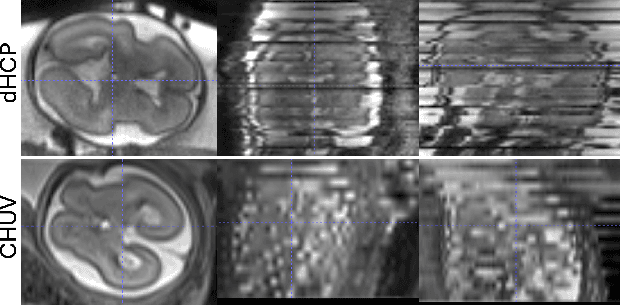

Abstract:Fetal brain MRI is becoming an increasingly relevant complement to neurosonography for perinatal diagnosis, allowing fundamental insights into fetal brain development throughout gestation. However, uncontrolled fetal motion and heterogeneity in acquisition protocols lead to data of variable quality, potentially biasing the outcome of subsequent studies. We present FetMRQC, an open-source machine-learning framework for automated image quality assessment and quality control that is robust to domain shifts induced by the heterogeneity of clinical data. FetMRQC extracts an ensemble of quality metrics from unprocessed anatomical MRI and combines them to predict experts' ratings using random forests. We validate our framework on a pioneeringly large and diverse dataset of more than 1600 manually rated fetal brain T2-weighted images from four clinical centers and 13 different scanners. Our study shows that FetMRQC's predictions generalize well to unseen data while being interpretable. FetMRQC is a step towards more robust fetal brain neuroimaging, which has the potential to shed new insights on the developing human brain.

Abstract:Quality control (QC) has long been considered essential to guarantee the reliability of neuroimaging studies. It is particularly important for fetal brain MRI, where large and unpredictable fetal motion can lead to substantial artifacts in the acquired images. Existing methods for fetal brain quality assessment operate at the \textit{slice} level, and fail to get a comprehensive picture of the quality of an image, that can only be achieved by looking at the \textit{entire} brain volume. In this work, we propose FetMRQC, a machine learning framework for automated image quality assessment tailored to fetal brain MRI, which extracts an ensemble of quality metrics that are then used to predict experts' ratings. Based on the manual ratings of more than 1000 low-resolution stacks acquired across two different institutions, we show that, compared with existing quality metrics, FetMRQC is able to generalize out-of-domain, while being interpretable and data efficient. We also release a novel manual quality rating tool designed to facilitate and optimize quality rating of fetal brain images. Our tool, along with all the code to generate, train and evaluate the model will be released upon acceptance of the paper.